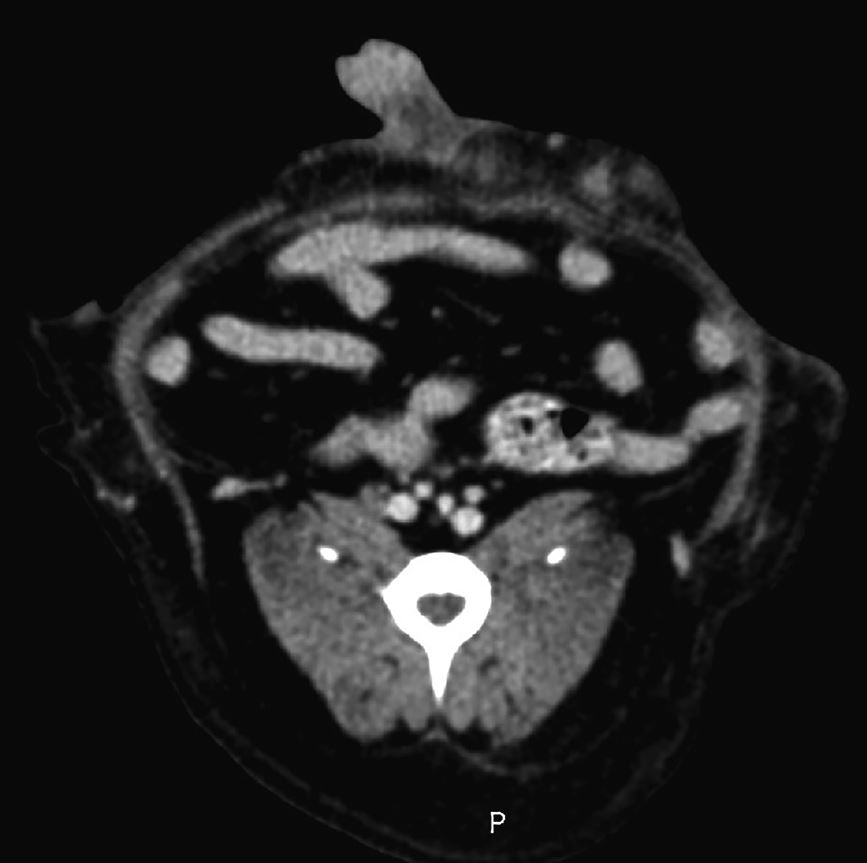

Für eine Ganzkörper-CT-Untersuchung wurde der Patient in Rückenlage verbracht und es wurden je eine native Aufnahme und eine Aufnahme nach intravenöser Kontrastmittelgabe angefertigt. Das CT zeigte 3 Unterhautknoten, je ca. 2 × 1 cm Durchmesser groß, abgrenzbar von der Bauchdecke und mit geringgradiger Kontrastmittelanreicherung [Abb. 3]. Es wurden keine weiteren organischen Veränderungen, insbesondere in der Pankreasregion, festgestellt.